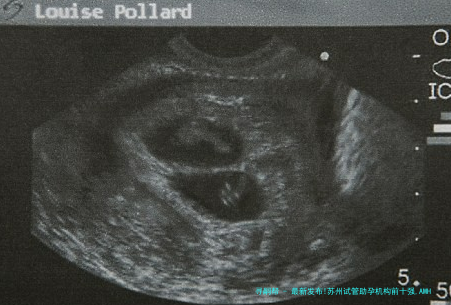

> 当一颗AMH 0.2 ng/毫升下的4AA级囊胚成功着床时,那些曾被宣判的“不可能”,终将在技术翻新中重写为生命的新章。